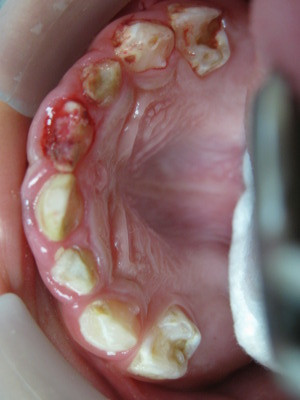

| Răng sữa sâu không quan trọng? Hoàn toàn sai. Răng sữa giữ chỗ cho răng vĩnh viễn. Nếu sâu răng ở răng sữa không được điều trị thì chúng có thể phát triển thành cơn đau nghiêm trọng và gây áp-xe. Đôi khi sự nhiễm trùng có thể lân lan sang các khu vực khác của cơ thể và trong một vài trường hợp hiếm có thể dẫn đến tử vong. |